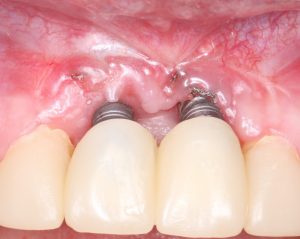

Помимо этого, один из этапов лечения периимплантита предполагает «превращение» субгингивального имплантата в трансгингивальный (подробности здесь>>). Описанную в статье методику можно считать успешной —  она, пусть и не восстанавливает уровень костной ткани вокруг имплантатов, но помогает избежать развития заболевания и потери имплантатов вообще: